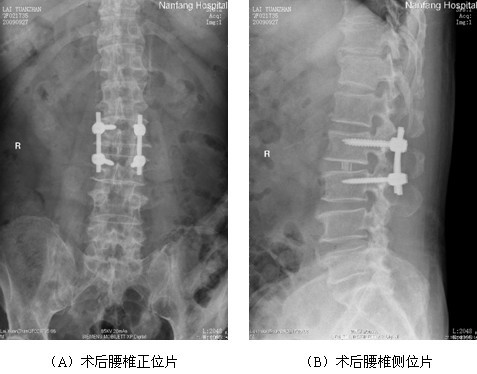

图3 腰椎内固定术后X线复查

(复查见腰2/3椎弓根螺钉位置良好,椎间cage位置佳,钛棒长度及曲度均适宜。)